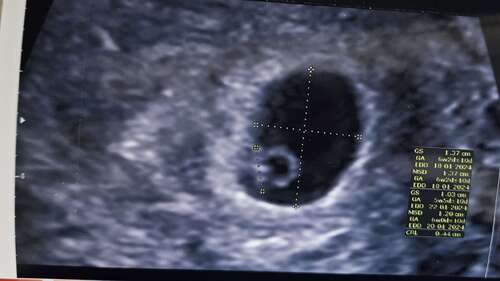

Je ziet een vruchtzakje, helemaal links groene lijn van boven na beneden is de 'baby' met een mooi kloppend hartje